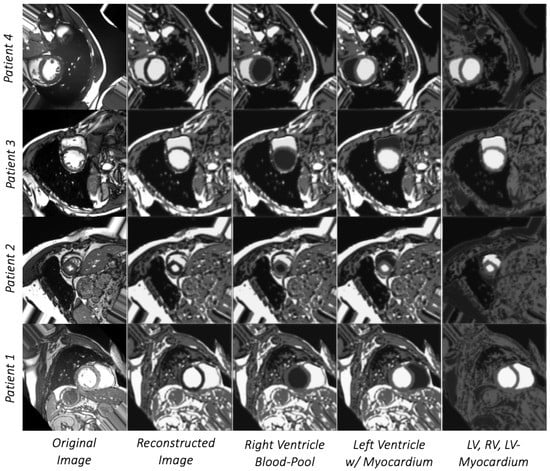

3.1. Image Segmentation Assessment